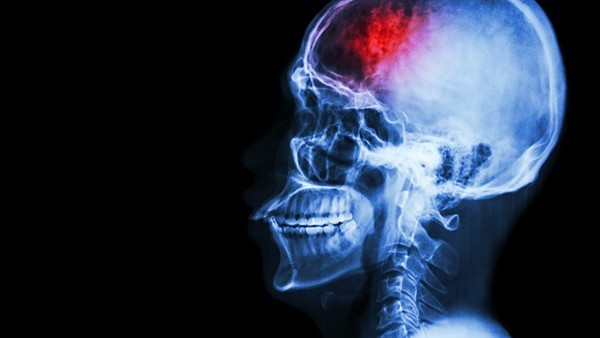

核磁共振指核磁共振成像,一般情况下,新生儿做磁共振成像,结果显示脑损伤,但临床无异常,这可能是损伤范围限定在特定区域、脑损伤情况轻微、损伤导致功能缺陷等因素引起的。具体分析如下:

1、损伤范围限定在特定区域:有时磁共振成像能够检测到在某一脑区的损伤,如果该损伤不包括与某种特定功能相关的脑区,一般不会对这项特定功能造成影响,所以新生儿不容易出现相关的临床症状。

2、脑损伤情况轻微:有时磁共振成像能够检测到非常的脑损伤,但这些损伤可能不会导致任何临床症状。若是这种情况,家长需要遵医嘱给新生儿做进一步检查。

3、损伤导致功能缺陷:有时脑损伤可以导致一个或多个临床功能缺陷,但部分缺陷可能在一段时间后才会发现,如果是这种情况,可以暂时观察。

除上述相对常见的因素外,还可能是其他因素引起的,如大脑皮层损伤、颅内感染、过度性病变等。建议家长及时带新生儿到医院治疗。